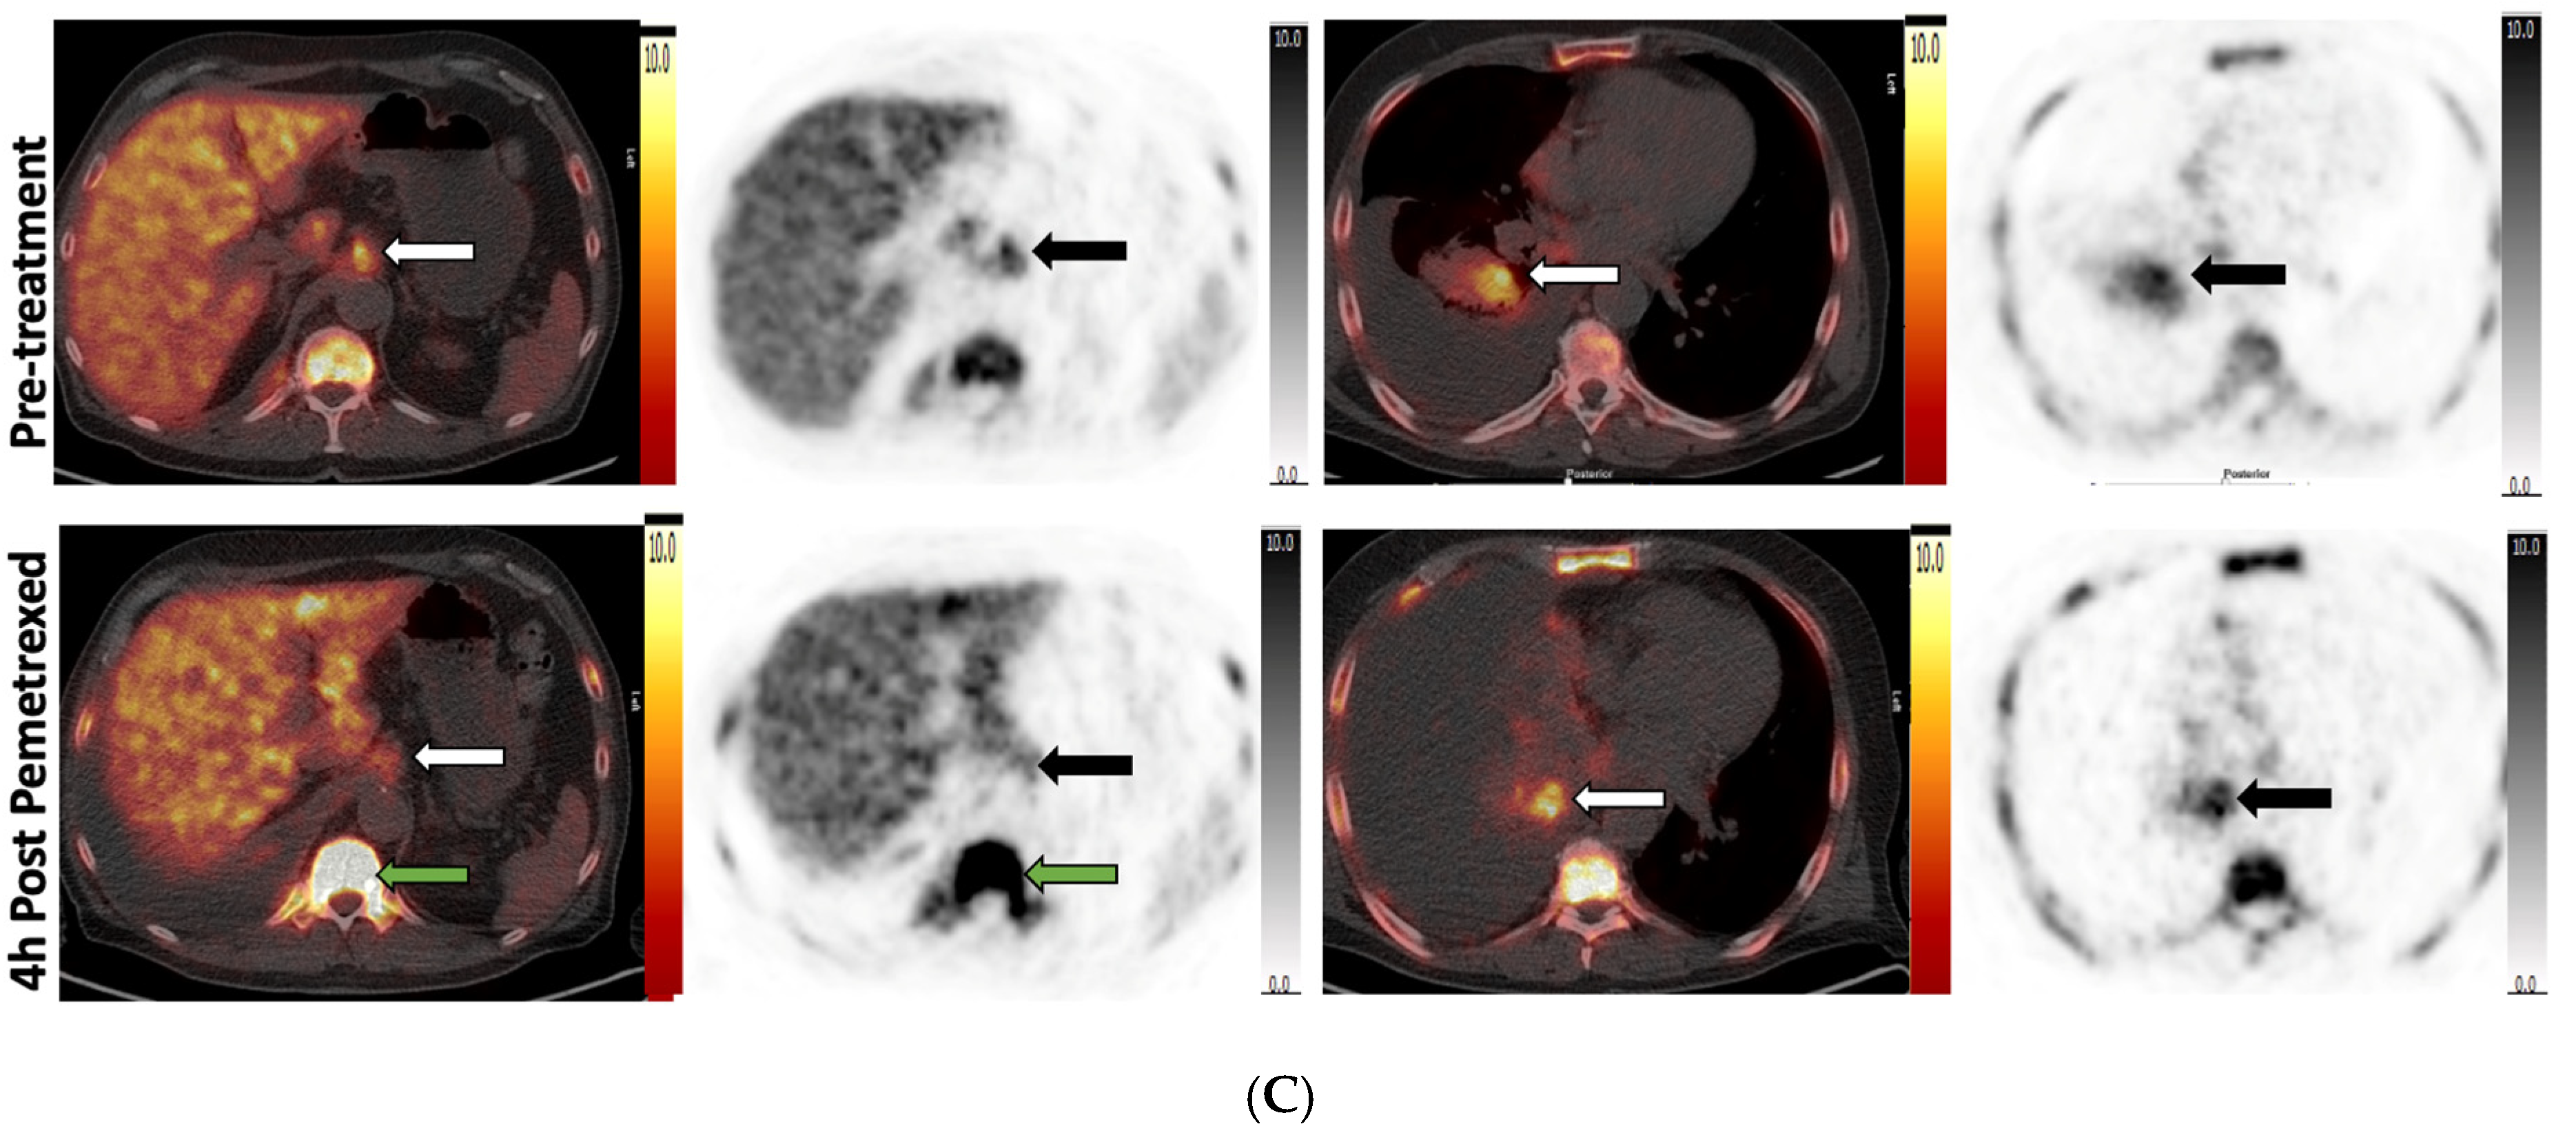

3.4. Pemetrexed Increased 18F-FLT Uptake in TS-Responsive Healthy Tissues